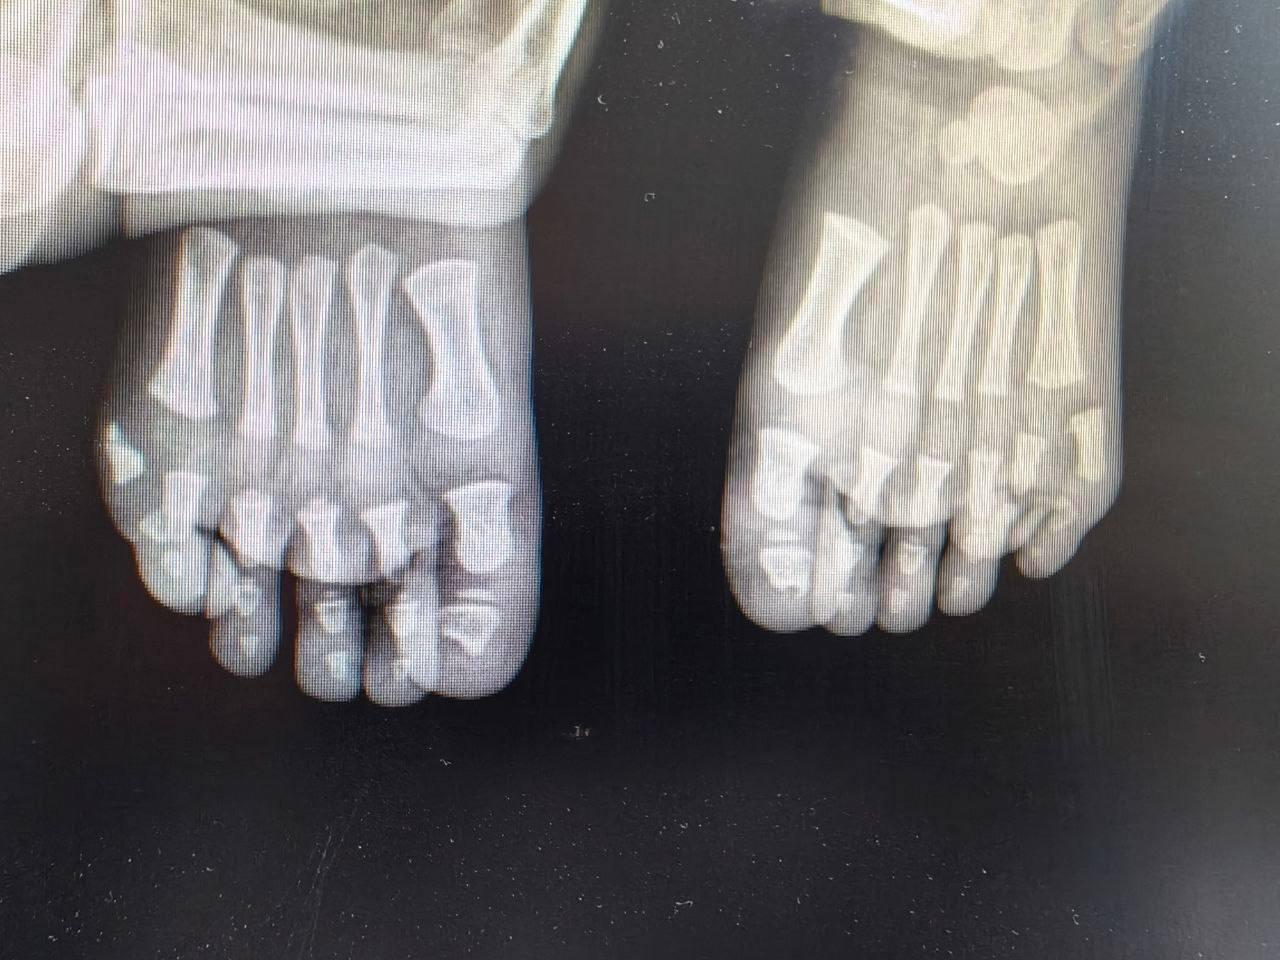

По шесть пальцев на каждой ноге — с такой особенностью родился мальчик в Подмосковье.

Дискомфорт был не только эстетический: подобрать обувь очень сложно, ходить в ней тоже. Поэтому родители обратились к врачам МОДКТОБ, где был поставлен диагноз — полидактилия.

На одной стопе лишний пальчик уже удалили. После полного восстановления медики проведут операцию на второй ноге.